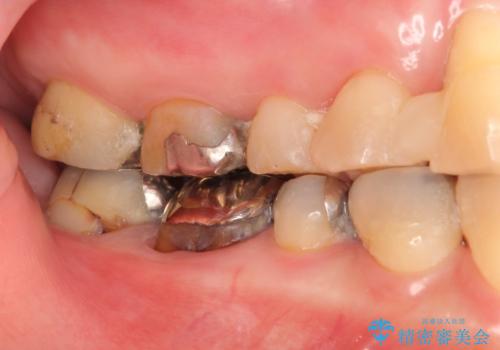

- 前歯を噛みしめにより失い、さらに犬歯もグラグラになり全く噛めなくなり改善を求めて来院されました。

過度な力がかかり周囲の骨に高度な吸収が見られた犬歯は抜歯し、機能・審美性の回復をより咬合力に対して抵抗力のあるブリッジ補綴にて対応します。

過度な咬合力は歯を失う元です。

ブリッジによる欠損補綴を行ったのち、ナイトガードを夜間装着していただき歯を守ります。